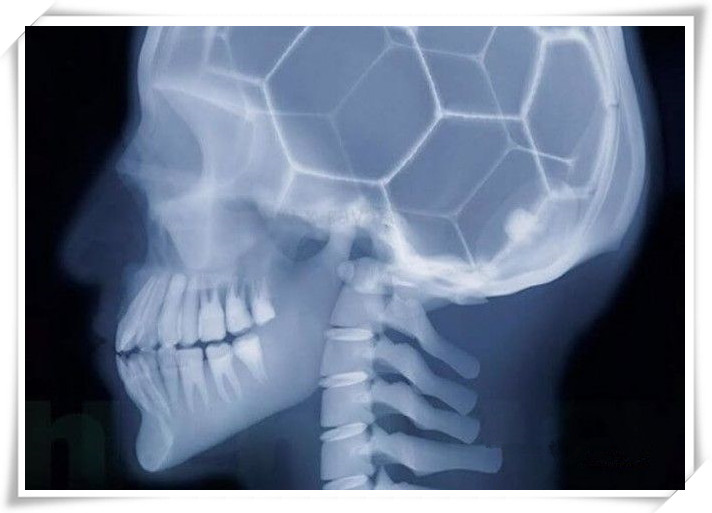

人的大脑看起来像一个足球